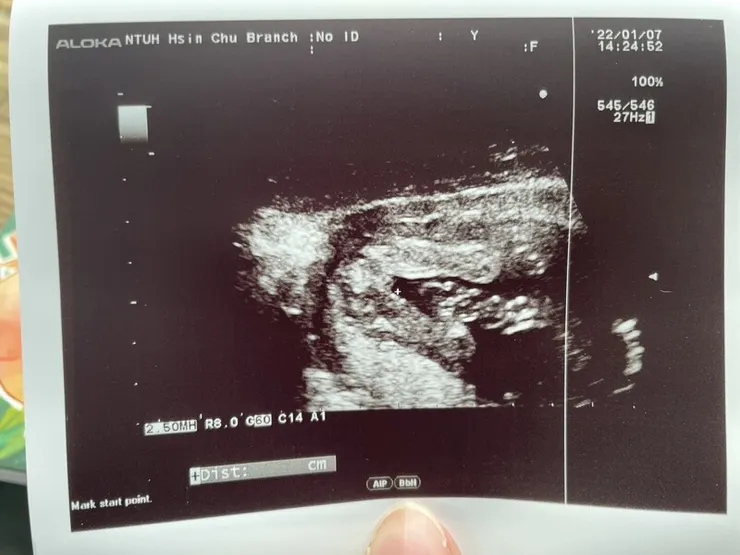

【第17周~性別公開】

哇~~~ 在第17周終於揭曉性別了...

爸爸的前世情人到來!!! 但爸爸的最愛還是媽媽才可以唷XD